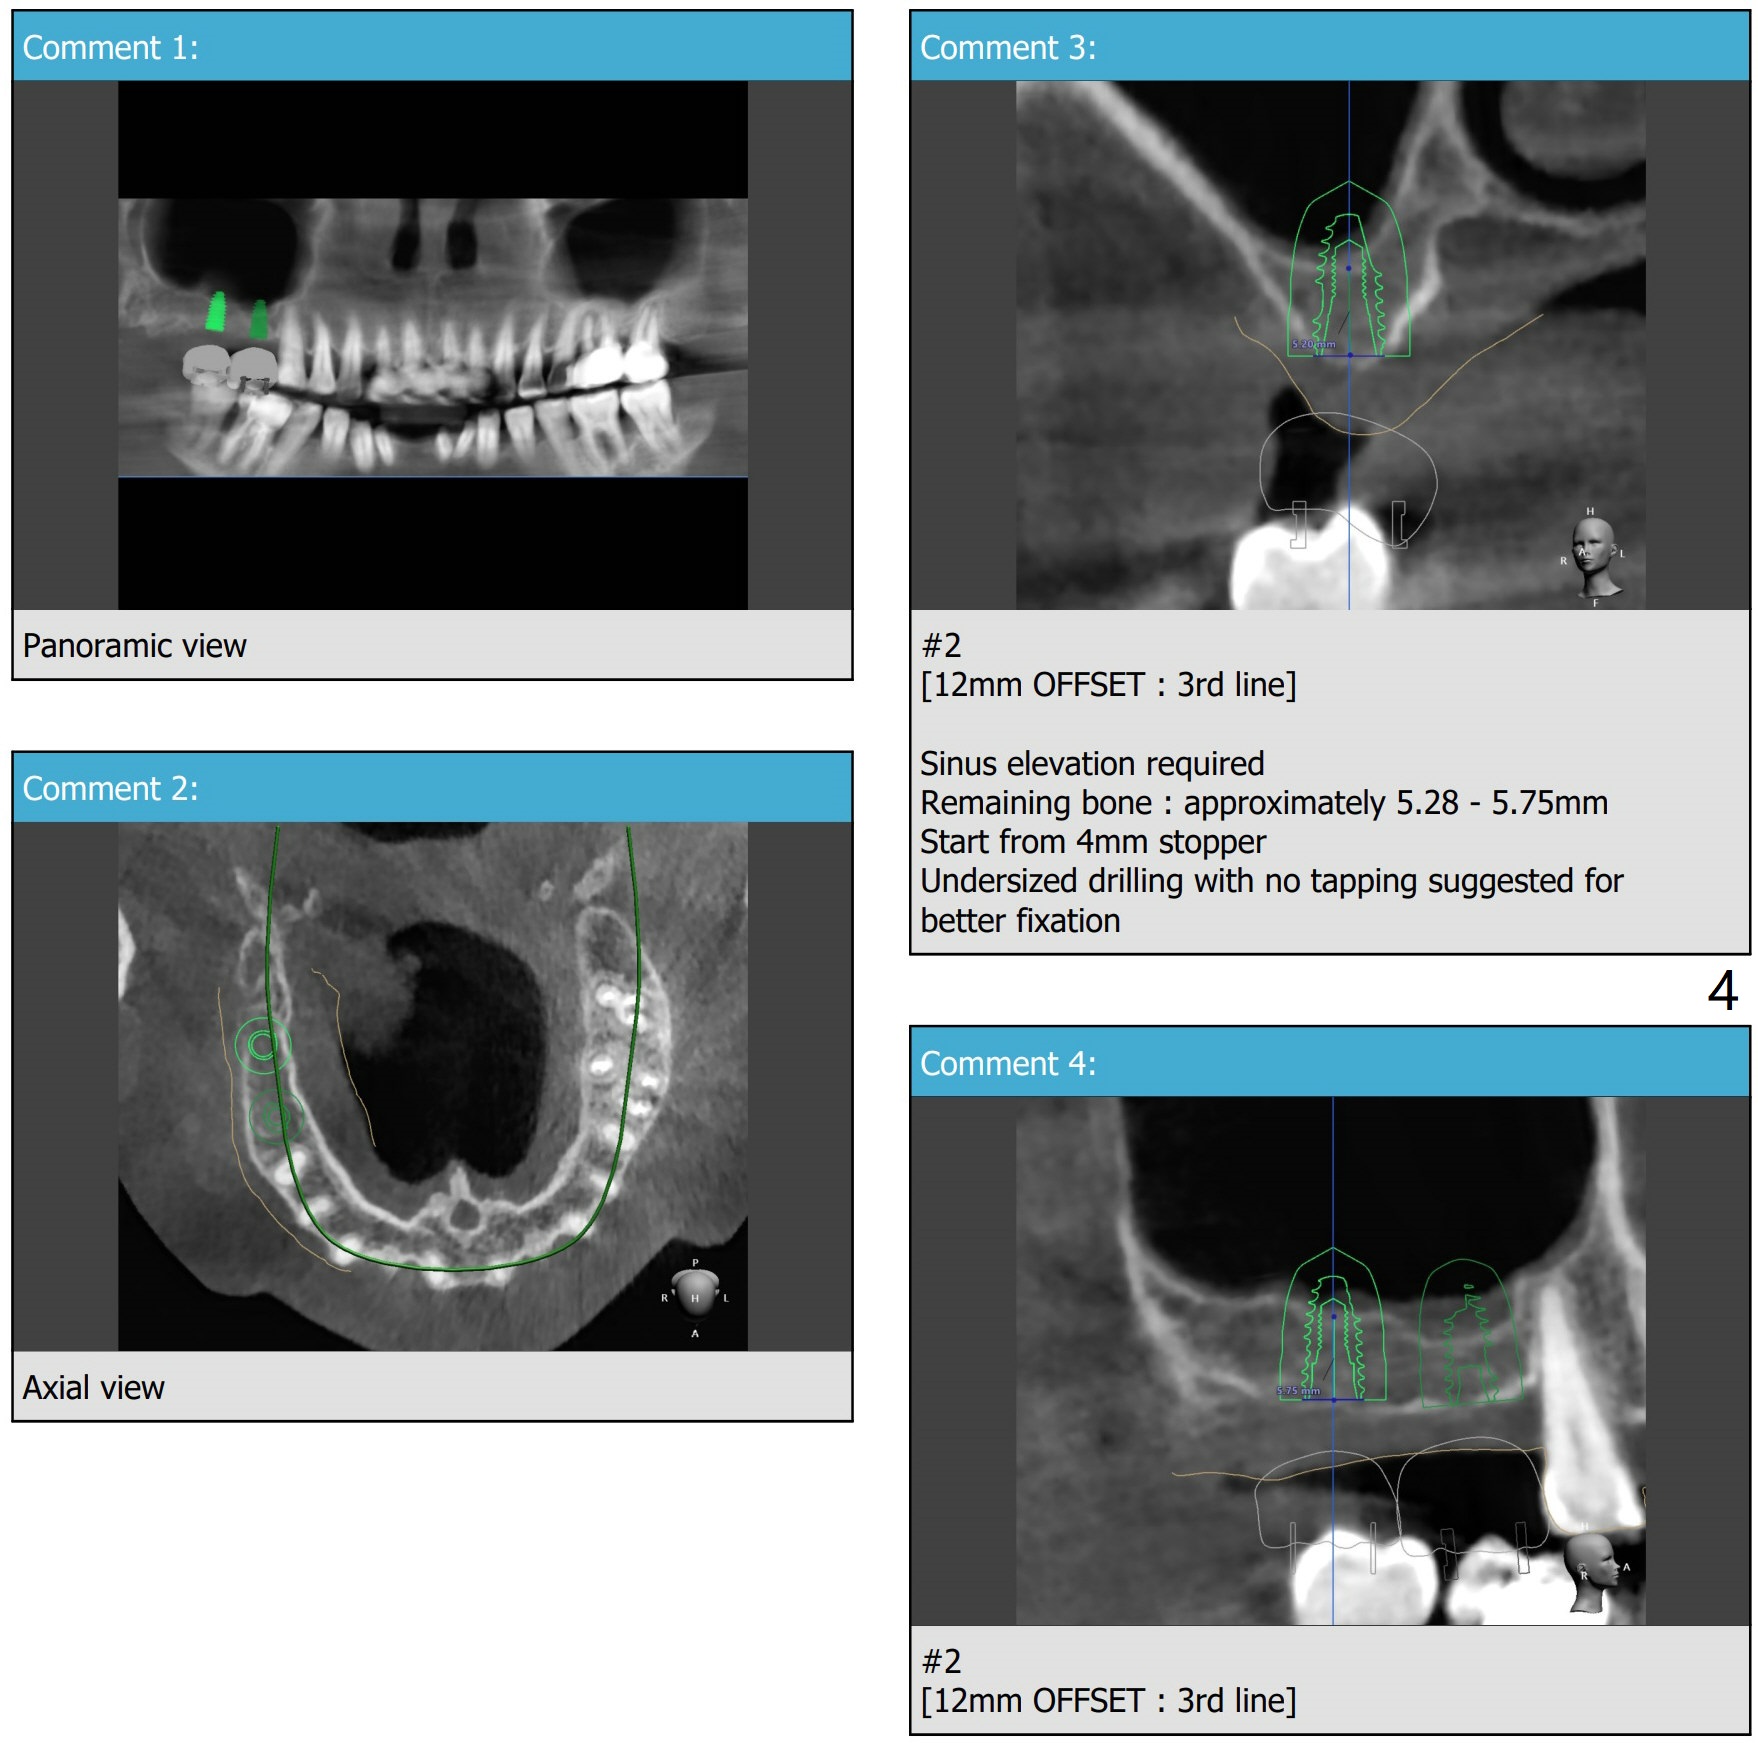

Narrow Implants with Lift